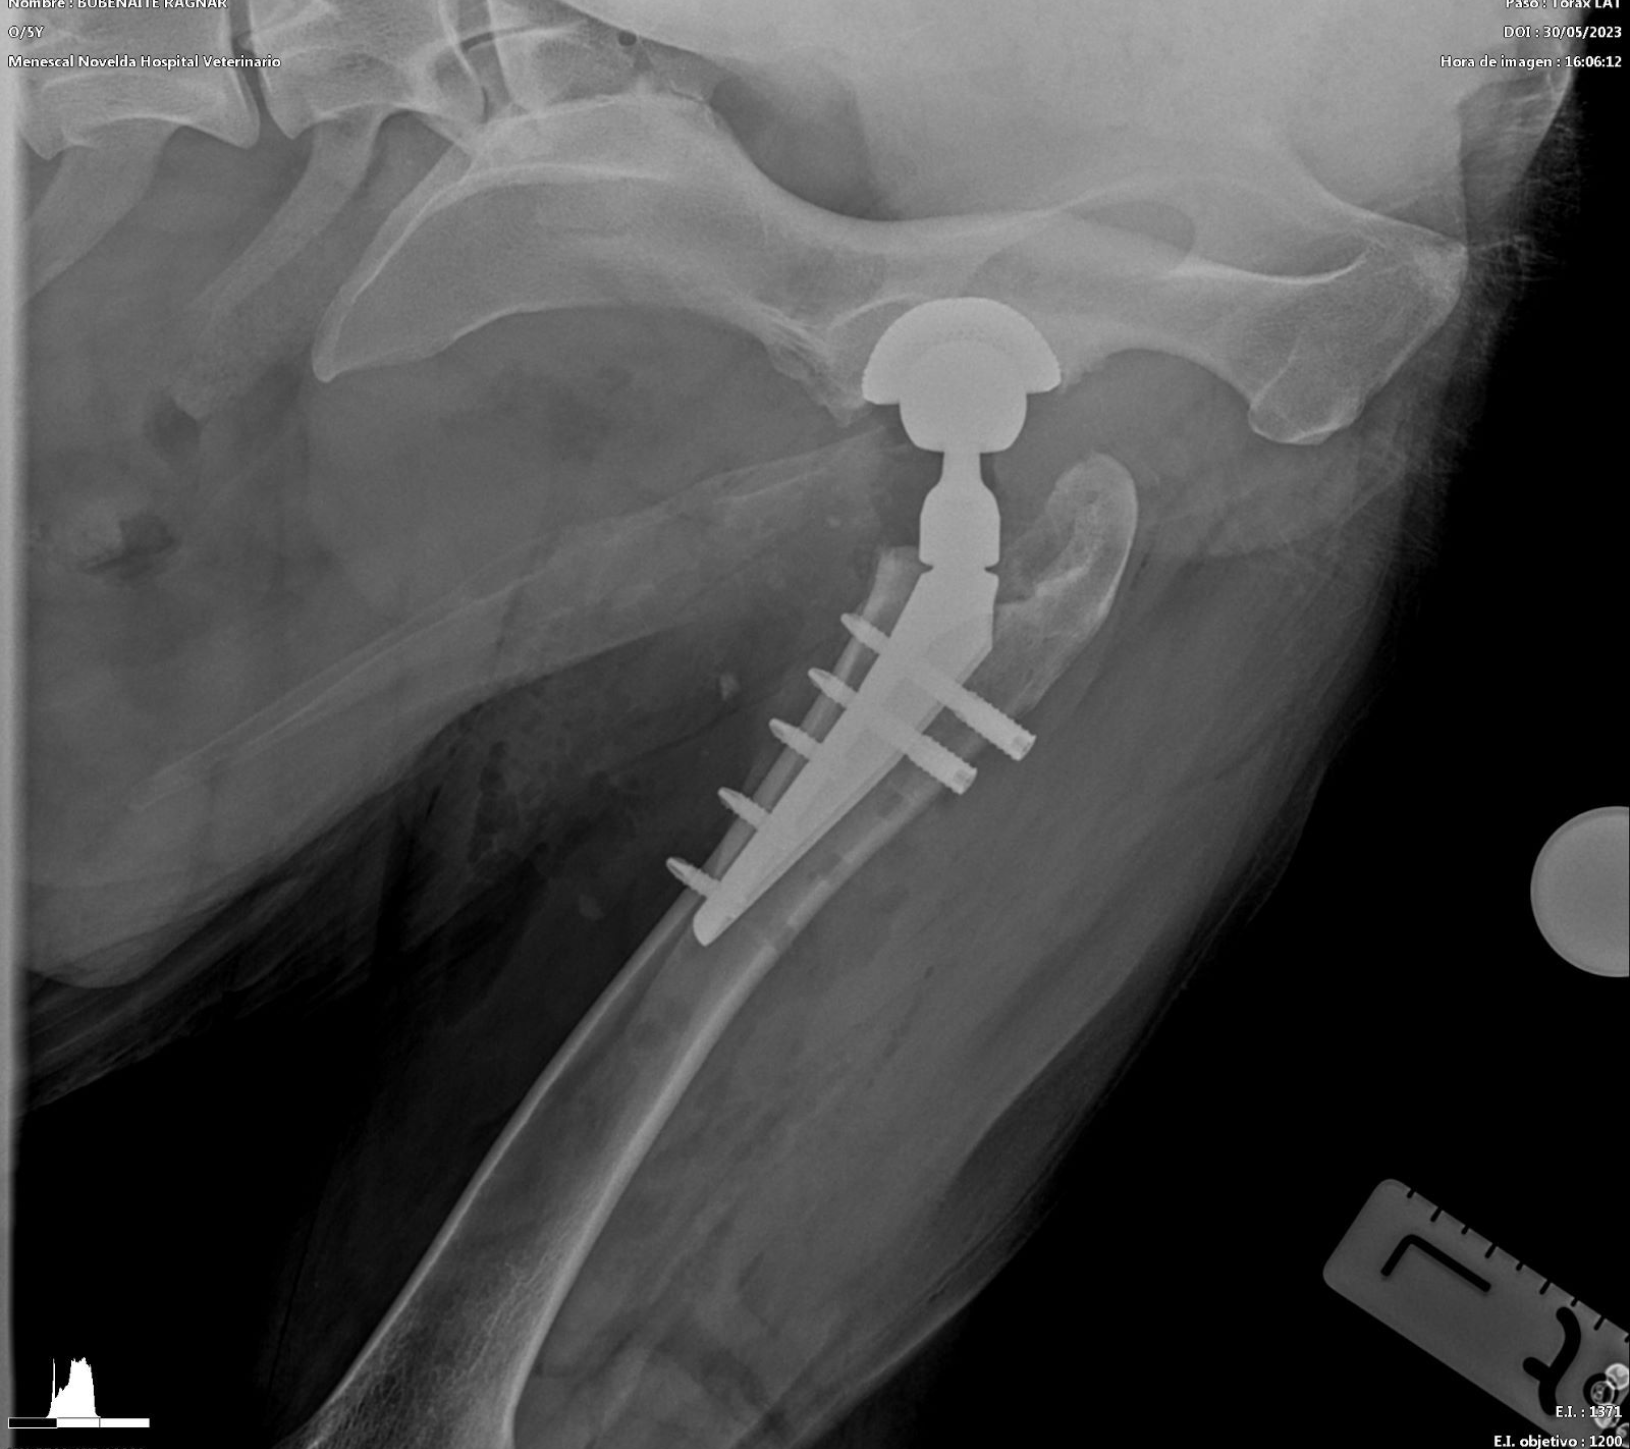

- Prótesis de cadera: es una técnica que generalmente se indica en pacientes adultos que padecen una enfermedad degenerativa articular (artrosis) avanzada. Consiste en la sustitución de los componentes acetabular y femoral afectados e involucrados en la articulación, por unos sintéticos, que permitirán una movilidad apropiada y sin dolor. Aunque es muy posible que un paciente necesite una prótesis en ambas caderas, nunca se realizarán de forma simultánea, espaciando las mismas el tiempo necesario para asegurar la recuperación de la primera. La mayoría de perros se encuentran bastante confortables pocos días después de la cirugía y vuelven a alcanzar niveles de actividad elevados unos meses más tarde.